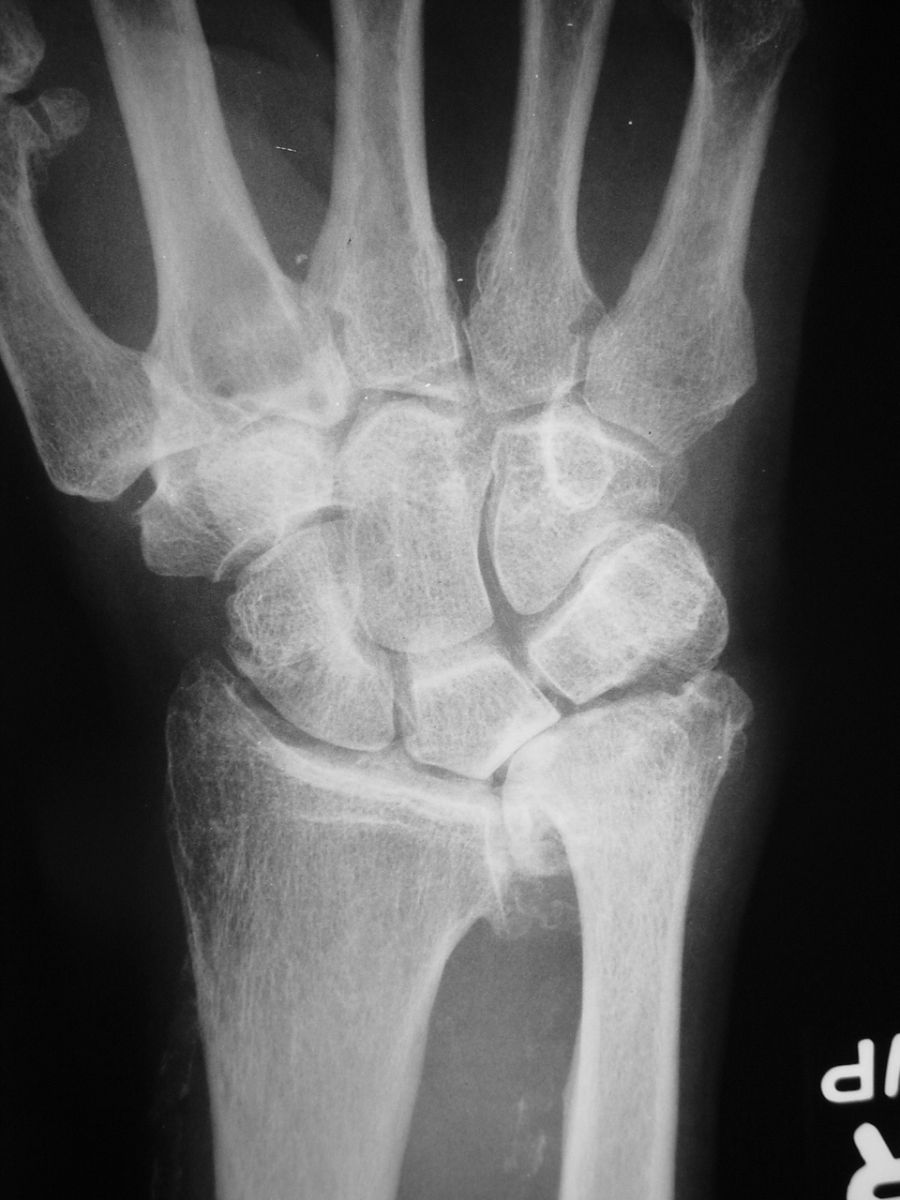

| Case 1. This 80 year old man developed wrist and elbow pain years after radial head excision for fracture. Radiographs show proximal migration of the radius resulting in valgus instability of the elbow, radiocapitellar impingement and distal ulnar impaction. This pattern of longitudinal forearm disruption, proximal radial fracture and dislocation of the distal radioulnar joint, is referred to as the Essex-Lopresti fracture dislocation. |